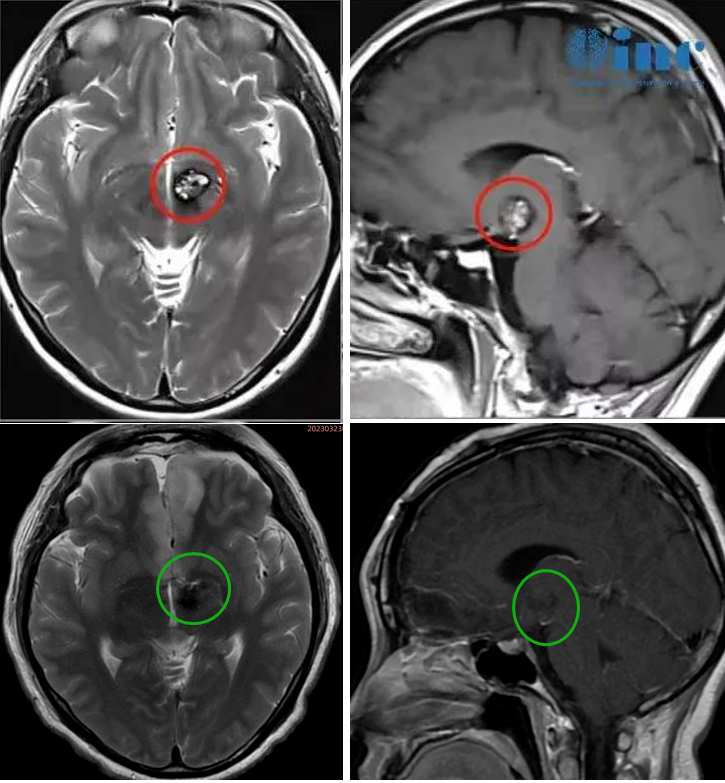

术前术后影像对比

3、肿瘤位置深在,术中导航容易因脑脊液释放引发漂移,术中需以前联合为解剖标记,肿瘤位于前联合后方

经纵裂入路(InterhemisphericCraniotomy)处理下丘脑、中脑病变。纵裂入路开颅术是利用大脑纵裂的自然间隙,进入到大脑镰旁中线深部和脑室旁部位。通过这个自然间隙操作有诸多优点,比如较大限度的降低了对脑组织的牵拉和侵犯。但缘于此操作通道深在而狭窄,该区域的手术充满了技术挑战。这个入路居于冠状缝周围(进行前纵裂入路时)或位于中央小叶的后方(进行顶上纵裂入路时),以保护冠状缝后3-4cm处的躯体感觉运动皮质和众多矢状窦旁优势静脉。

图:经纵裂入路